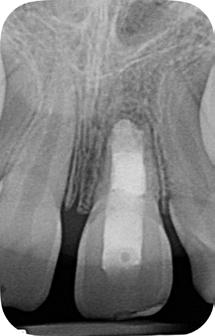

En la segunda sesión, 15 días después, realizamos la obturación convencional del tercio apical del canal con gutapercha, llenado de la cavidad reabsortiva con BIO-C ® REPAIR (Angelus, Londrina - Brasil) (Figura 7, 8 y 9), condensándolo contra las paredes con condensadores específicos y bolita de algodón humedecida y realizamos el sellado coronario con resina.

El BIO-C® REPAIR es un cemento reparador biocerámico listo para su uso. Se compone de silicato de calcio, aluminato de calcio, óxido de calcio, óxido de zirconio, óxido de hierro, dióxido

de silicio y agente de dispersión. El BIO-C® REPAIR presenta características superiores de adaptación marginal, biocompatibilidad, excelente radiopacidad y capacidad selladora en ambientes húmedos. Además de estas características, tiene como gran ventaja su facilidad de inserción a la cavidad reabsortiva

Figura 7 - BIO-C ® REPAIR (Angelus, Londrina - Brasil).

8 - Radiografia final

9 - Cavidad reabsortiva rellenada com BIO-C® REPAIR